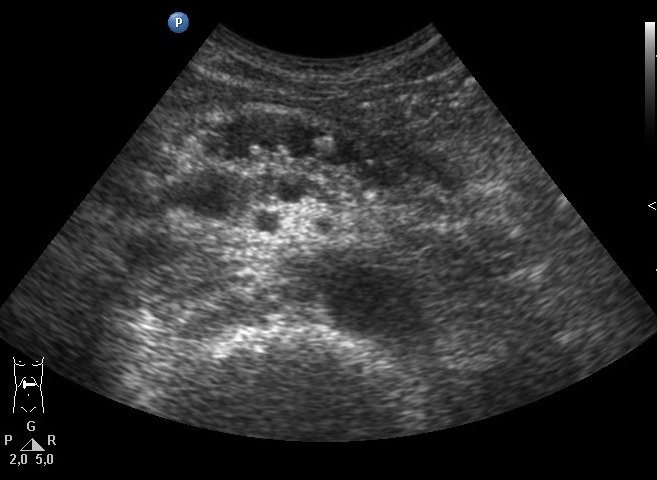

Есть два вида кистозных опухолей поджелудочной железы: доброкачественная микроцистная аденома и злокачественна макроцистная аденома. Микроцистная аденома состоит из множества мелких кист и на УЗИ выглядит как плотное образование. Макроцистная аденома, как правило, включает менее пяти кист размером более 20 мм. Иногда в таких кистах можно разглядеть полипоидные образования.

Кальцификаты в поджелудочной железе на УЗИ

Кальцификаты внутри поджелудочной железы могут давать акустическую тень, однако если они имеют маленькие размеры, то выглядят отдельной яркой эхоструктурой без акустической тени. При хроническом панкреатите кальцификаты распределены диффузно по всей поджелудочной железе. Камни в протоке располагаются по ходу протока. Желчные камни в дистальном холедохе могут быть oшибочно приняты за кальцификаты в поджелудочной железе. Кальцификаты хорошо видно на КТ, а для необызвествленных камней предпочтительно МРТ или УЗИ.

| Фото. А — В расширенном протоке небольшой камень. Б — В расширенном протоке поджелудочной железы ряд из нескольких камней с затенением позади. В — У больного с хроническим панкреатитом огромные камни в расширенном протоке. Обратите внимание на интенсивное затенение позади. | ||